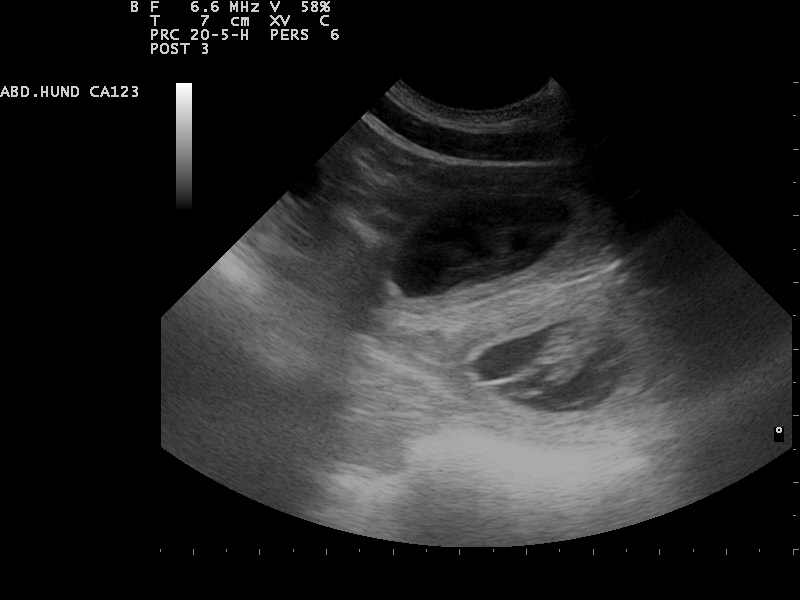

Hierfür eignet sich sehr gut die Gabe von Welpenfutter. Zu diesem Zeitpunkt kann mit einer Ultraschalluntersuchung

der Zustand der Trächtigkeit festgestellt werden. Besprechen Sie mögliche Risiken einer solchen Untersuchung mit dem Tierarzt.

Am 01.07.2014 waren wir zur Ultraschalluntersuchung und konnten

die ersten Bilder unserer Welpen bewundern.